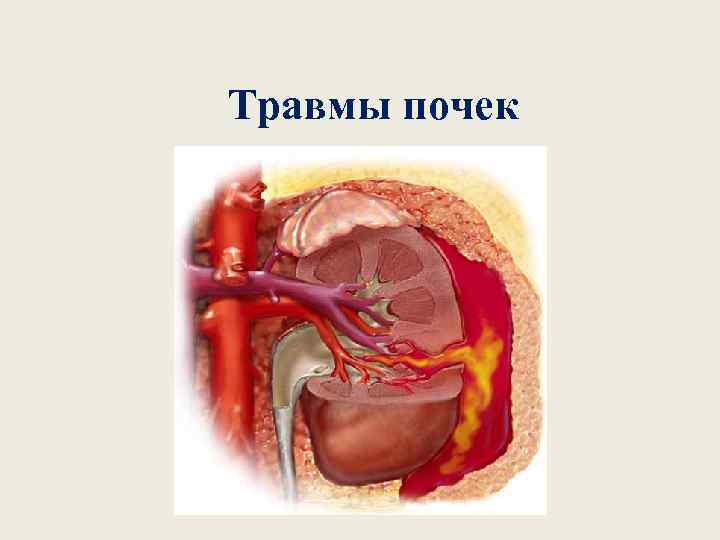

Травмы почек